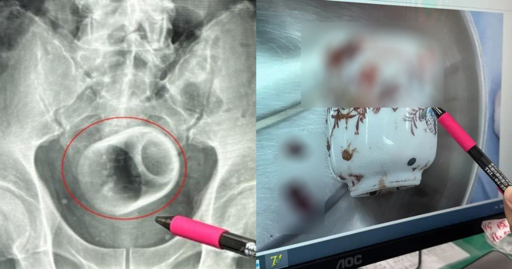

Man in Taiwan somehow gets 8cm by 6cm ceramic cup in bottom, claims it got there 'by accident'

He needed an abdominal surgery to remove it.